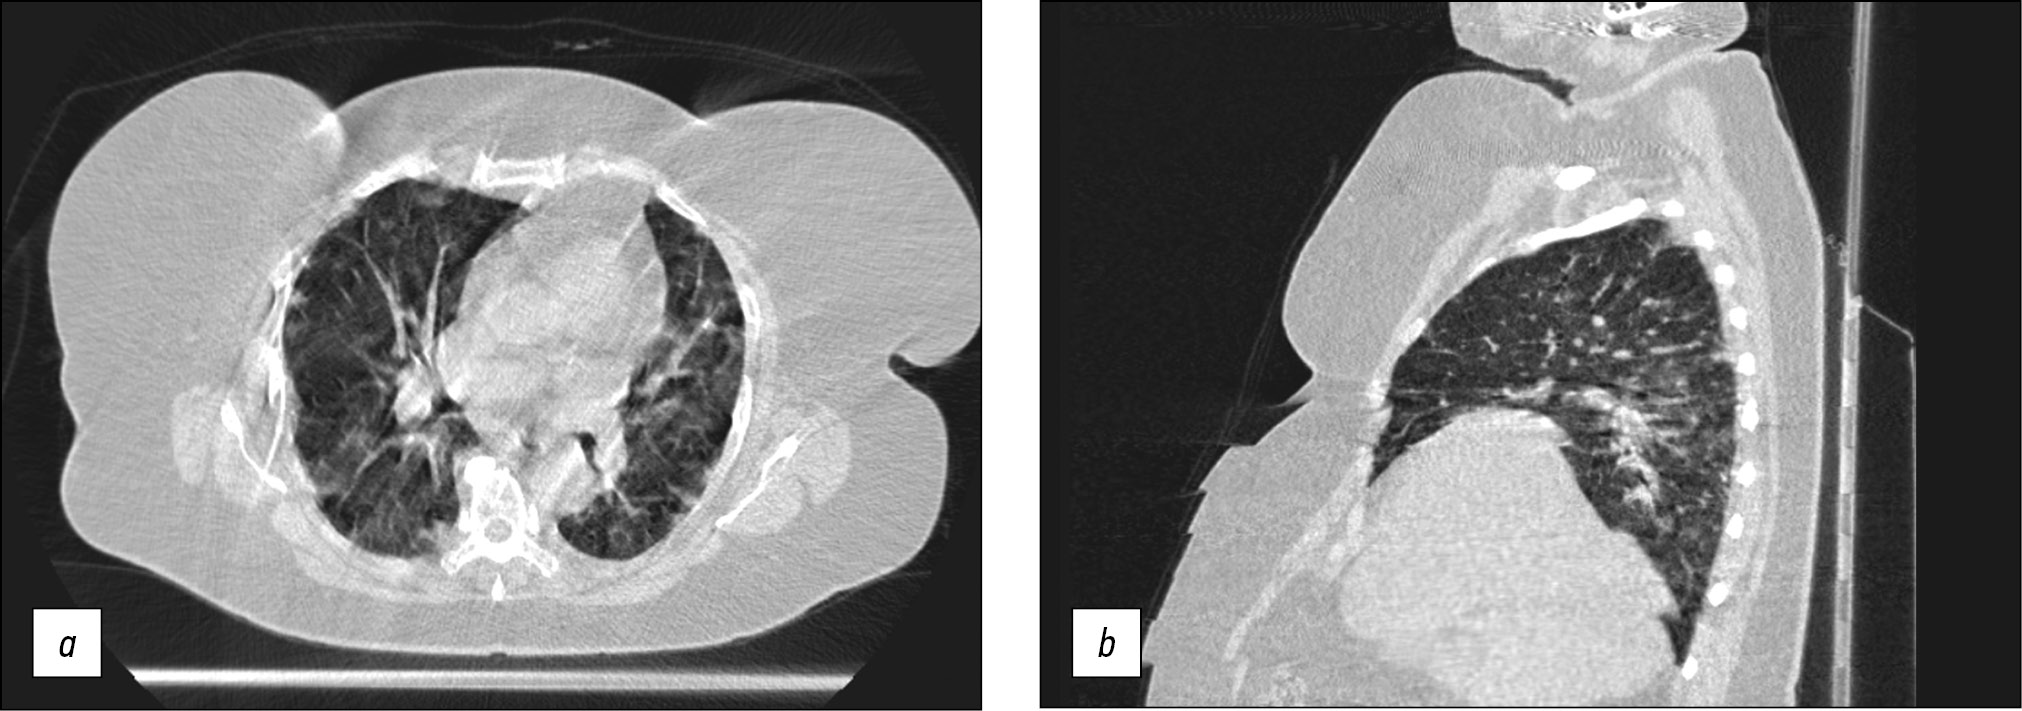

Long-term (15–25 s) scanning was too long for patients with respiratory insufficiency to remain their breath for the entire examination compared with stationary CT (3–5 s). As a result, motion artifacts (Fig. 6a) and steps (Fig. 6b) were present in CT images produced by breathing motions of the chest (Fig. 6).

Fig. 6. Axial and sagittal computed tomographic slices of chest organs in the lung window: (a) motion artifacts and (b) step artifacts caused by respiratory chest movements during scanning.